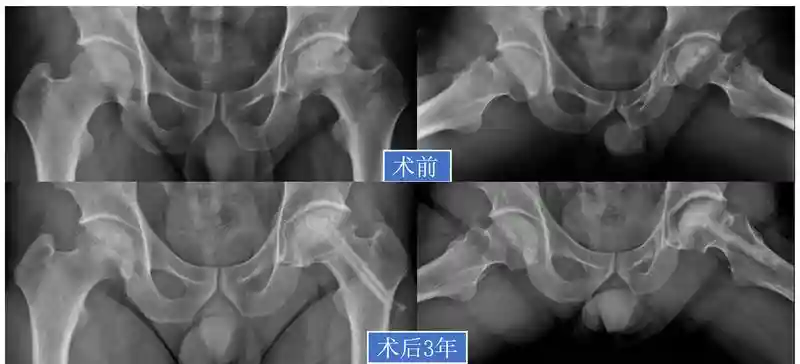

33岁陈先生也是因为经常饮酒而患上了双侧股骨头坏死,特别是左髋一走路就疼痛难忍,导致他不能正常工作。陈镇秋教授为他详细检查后,发现他的股骨头坏死已经影响了外侧柱,进一步塌陷的几率很大,因此不适合保守治疗,但是也还没有到必须换人工关节的地步。

陈镇秋教授为他采用微创保髋方法,坏死病灶清除+打压植骨+异体腓骨支撑术,相当于加固房子的“大梁”,预防塌陷加重。

术后3年回访,陈先生坏死的部分已经修复,走路不再感觉疼痛,活动自如。